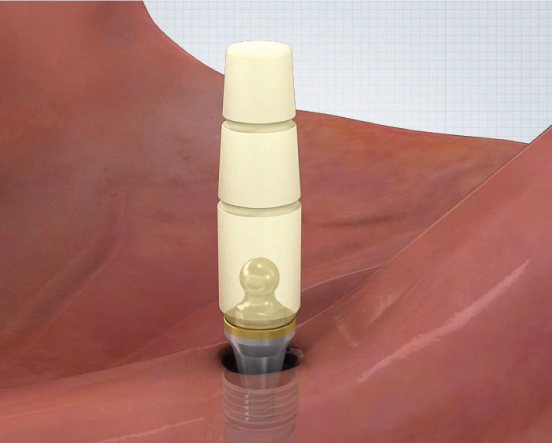

Direct Technique

①

- Healing Abutment 제거- Plastic Carrier을 이용하여 EZ LOCK Abutment 체결

▼

②

- EZ LOCK 전용드라이버를 이용하여 EZ LOCK 체결 (25N~)▼